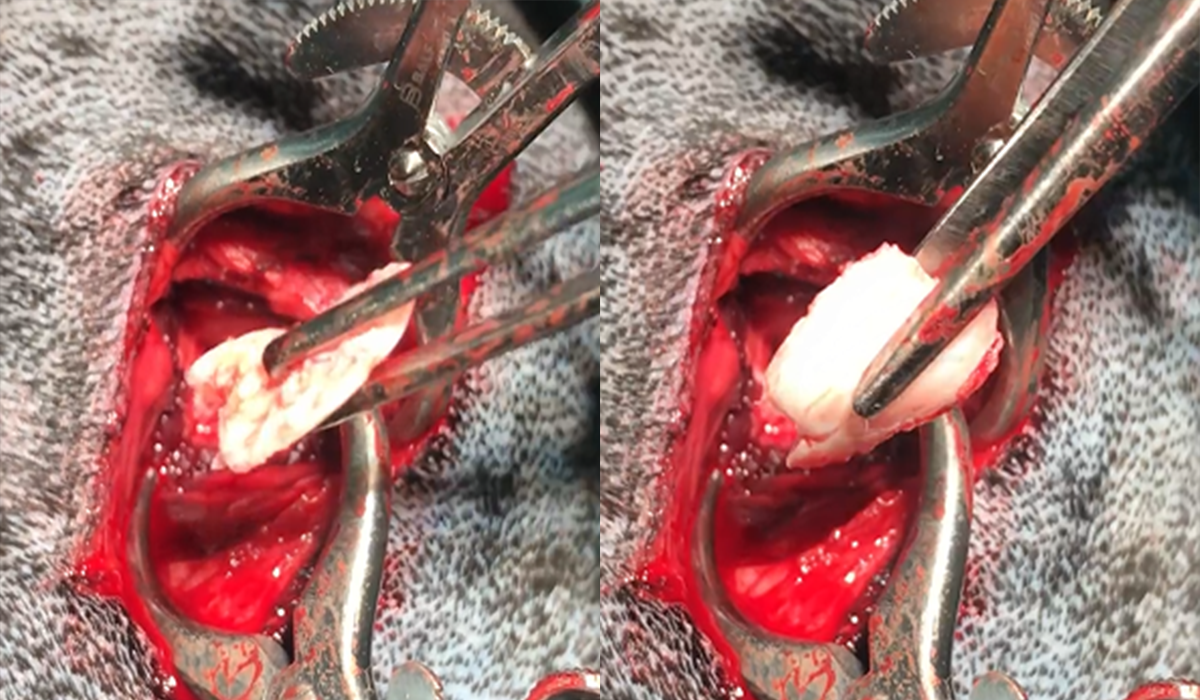

Пример из практики Кардаш М.А.: как выглядит отслоившийся хрящ во время операции.

Основное лечение заключается в хирургическом вмешательстве. Операция предполагает удаление отслоенного хрящевого фрагмента, который не рассосётся сам по себе. Без этого удаления хромота и разрушение сустава будут продолжаться. Каждый может представить себе ситуацию, когда камушек попадает под пятку обуви: пока его не уберёшь, облегчения не будет. Так же обстоит дело и с разрывом околосуставной хрящевой ткани.